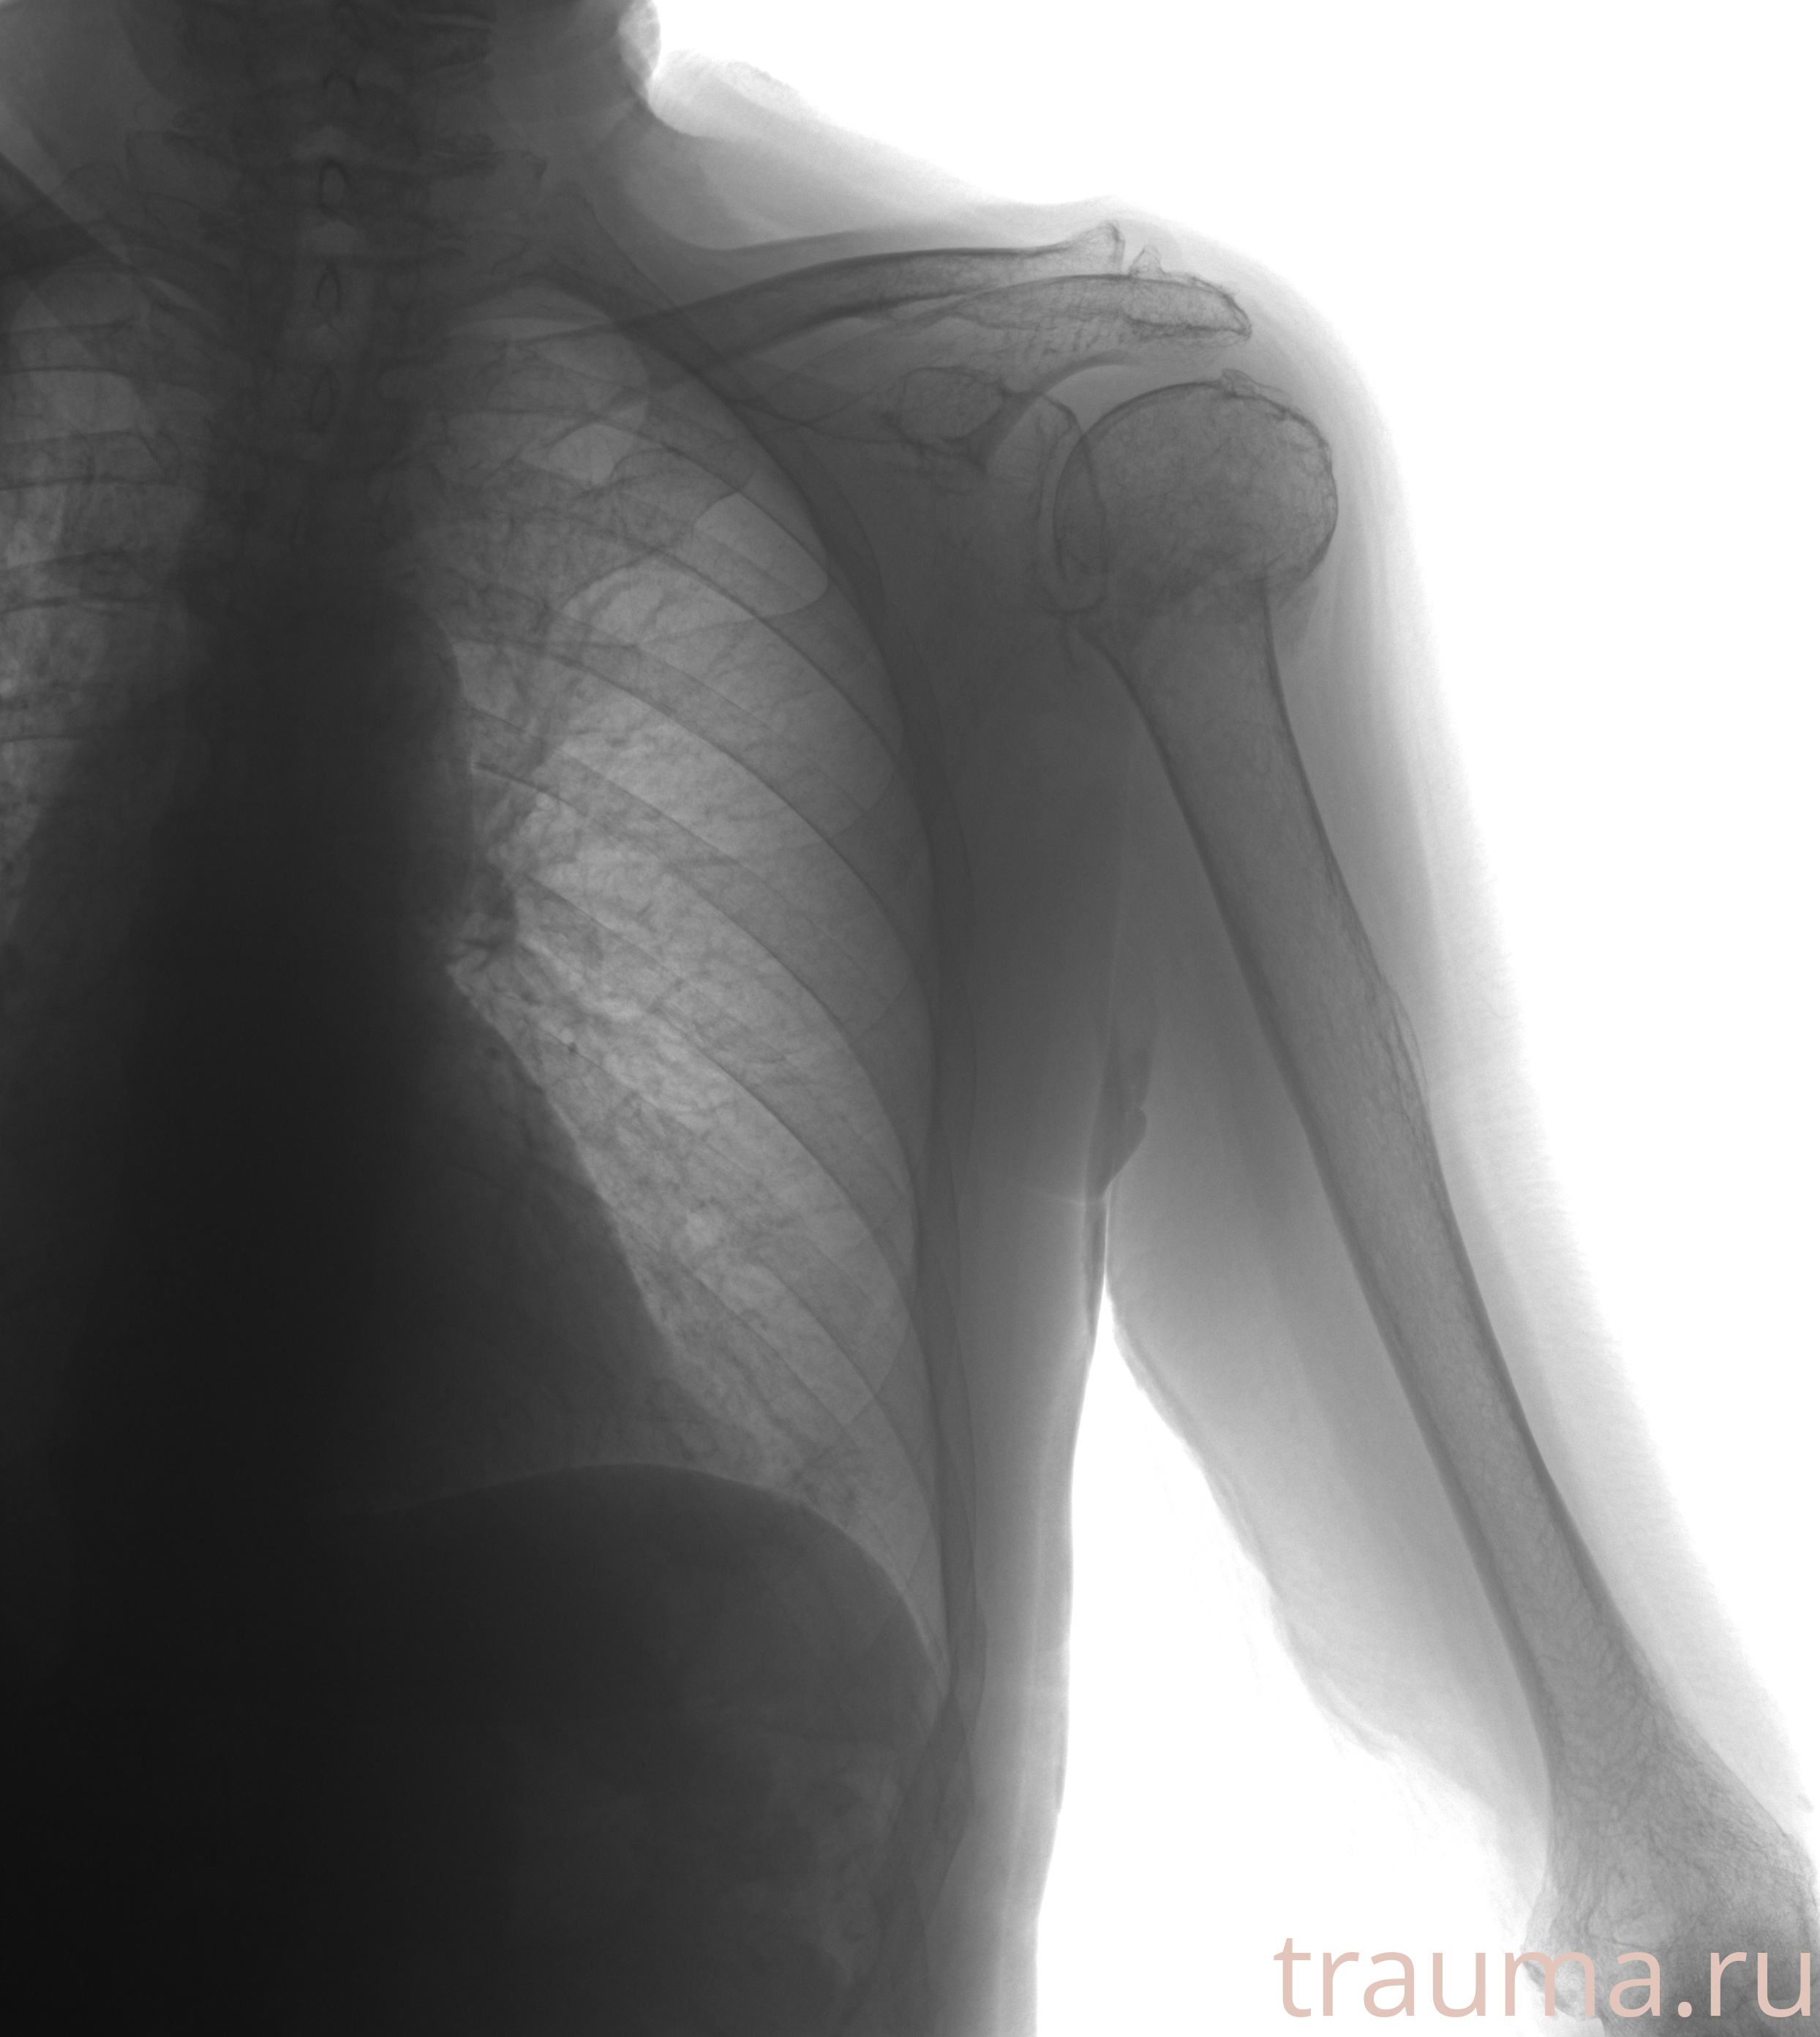

Рентген на дому: по вашему адресу приезжает врач-рентгенолог, травматолог-ортопед с мобильным рентгеновским аппаратом, проводит диагностику травмы или заболевания, делает необходимые рентгенограммы, дает рекомендации по дальнейшему лечению. Получить качественные снимки в домашних условиях возможно благодаря уникальной методике, разработанной МосРентген Центром для института  Склифосовского